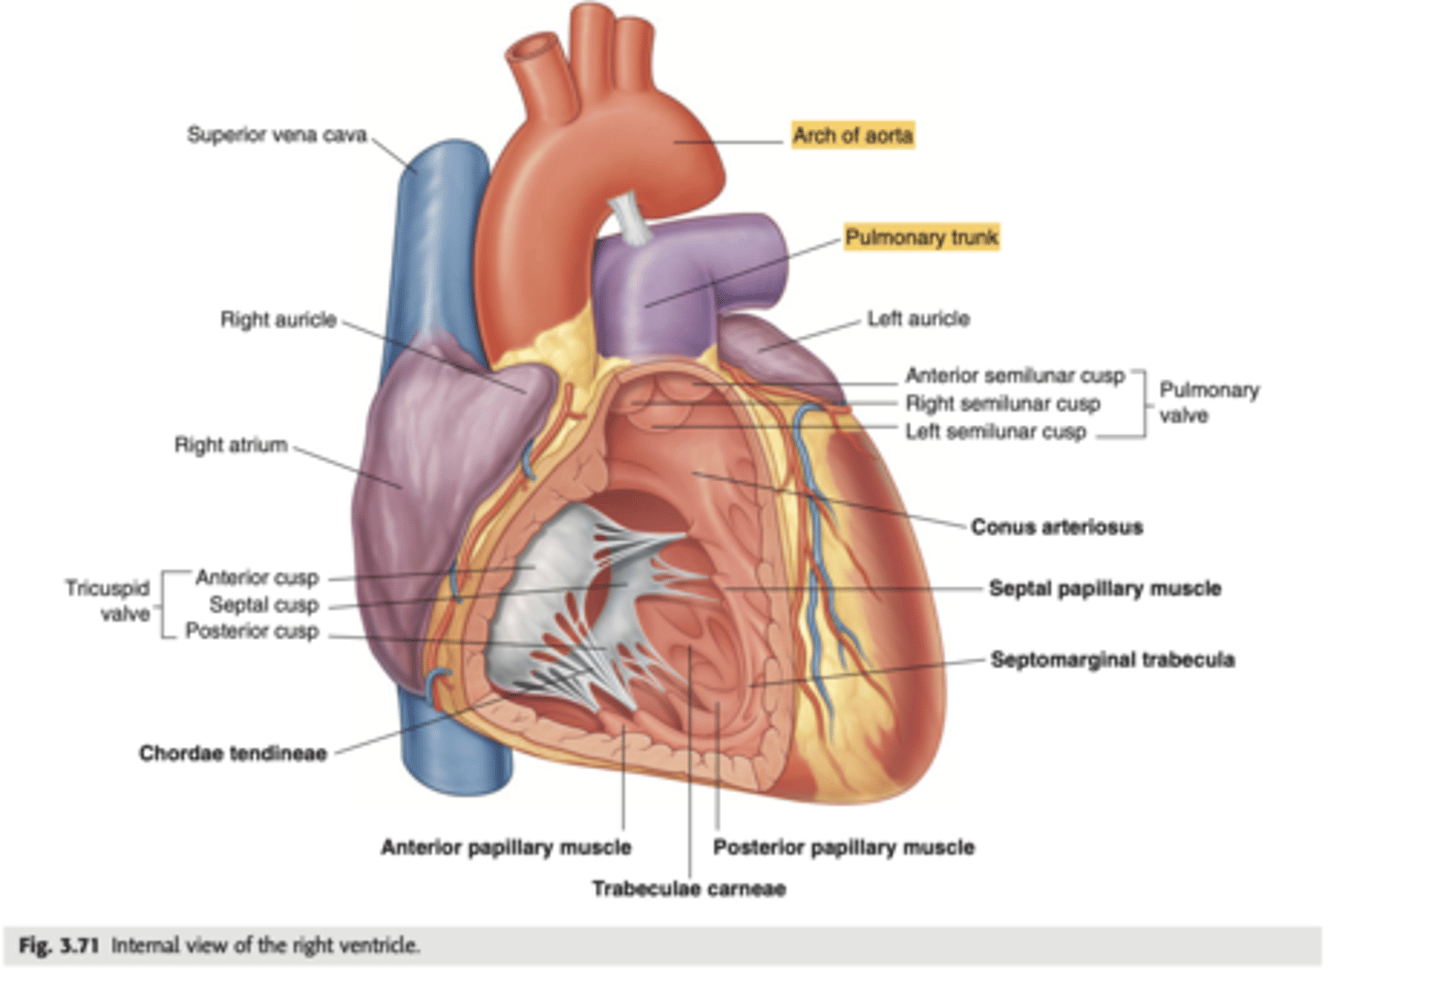

What are the walls of the right ventricle?

. Anterior wall

. Posterior wall

. Septal wall

Right ventricle has a conical shape with 2 o 3 walls

Describe the two portions of the medial/septal face/wall of the right ventricle.

infundibulum or outflow region or conus arteriosus (smooth and membranous)

trabeculae carnae (muscular and irregular)

What are the 3 cusps of the tricuspid valve?

Anterior

Posterior

Septal

What connect the cusps of the valve a to papillary muscles in the

right ventricle?

Chordae tendinae

With the contraction of the walls of the ventricle what's the action of the papillary muscles?

contract as well

With the contraction of papillary muscles what will be happen with the valve?

Close

What is the septomarginal trabeculae (or moderator band)?

Part of the conduction system of the heart.

electrical waves pass through this band to reach the papillary muscles.

LANDMARK

What are the positions of the pulmonary valve cusps?

Anterior

Right

Left

What are the 3 parts of the pulmonary valve?

. Nodules. (little point at the center)

. Lunules (from the nodule to the wall)

. Sinus (left in between)